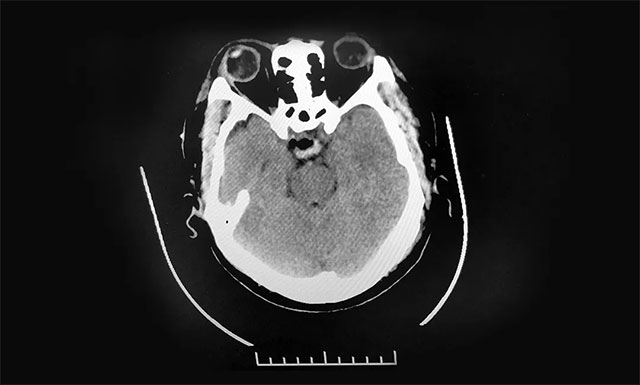

▲ 术后影像显示肿瘤被切除